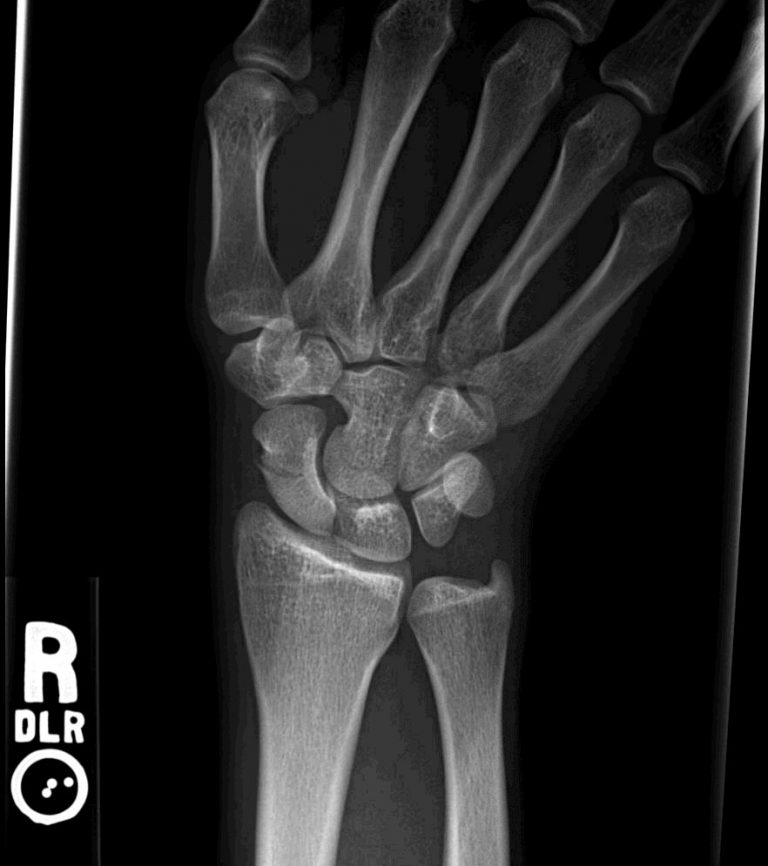

Scaphoid fracture Radiology Cases Scaphoid Fracture In Sport Scaphoid fracture is the most commonly fractured carpal bone in the athletic patient, accounting for over 85% of all. Most can be treated with cast immobilization, with an expected rate of union of 90% to 95%. Fractures are the most common wrist injuries,. The scaphoid is the most common carpal bone fracture in athletes and accounts for up to 70%. Scaphoid Fracture In Sport.